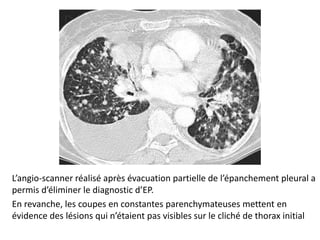

L’angio-scanner réalisé après évacuation partielle de l’épanchement pleural a

permis d’éliminer le diagnostic d’EP.

En revanche, les coupes en constantes parenchymateuses mettent en

évidence des lésions qui n’étaient pas visibles sur le cliché de thorax initial